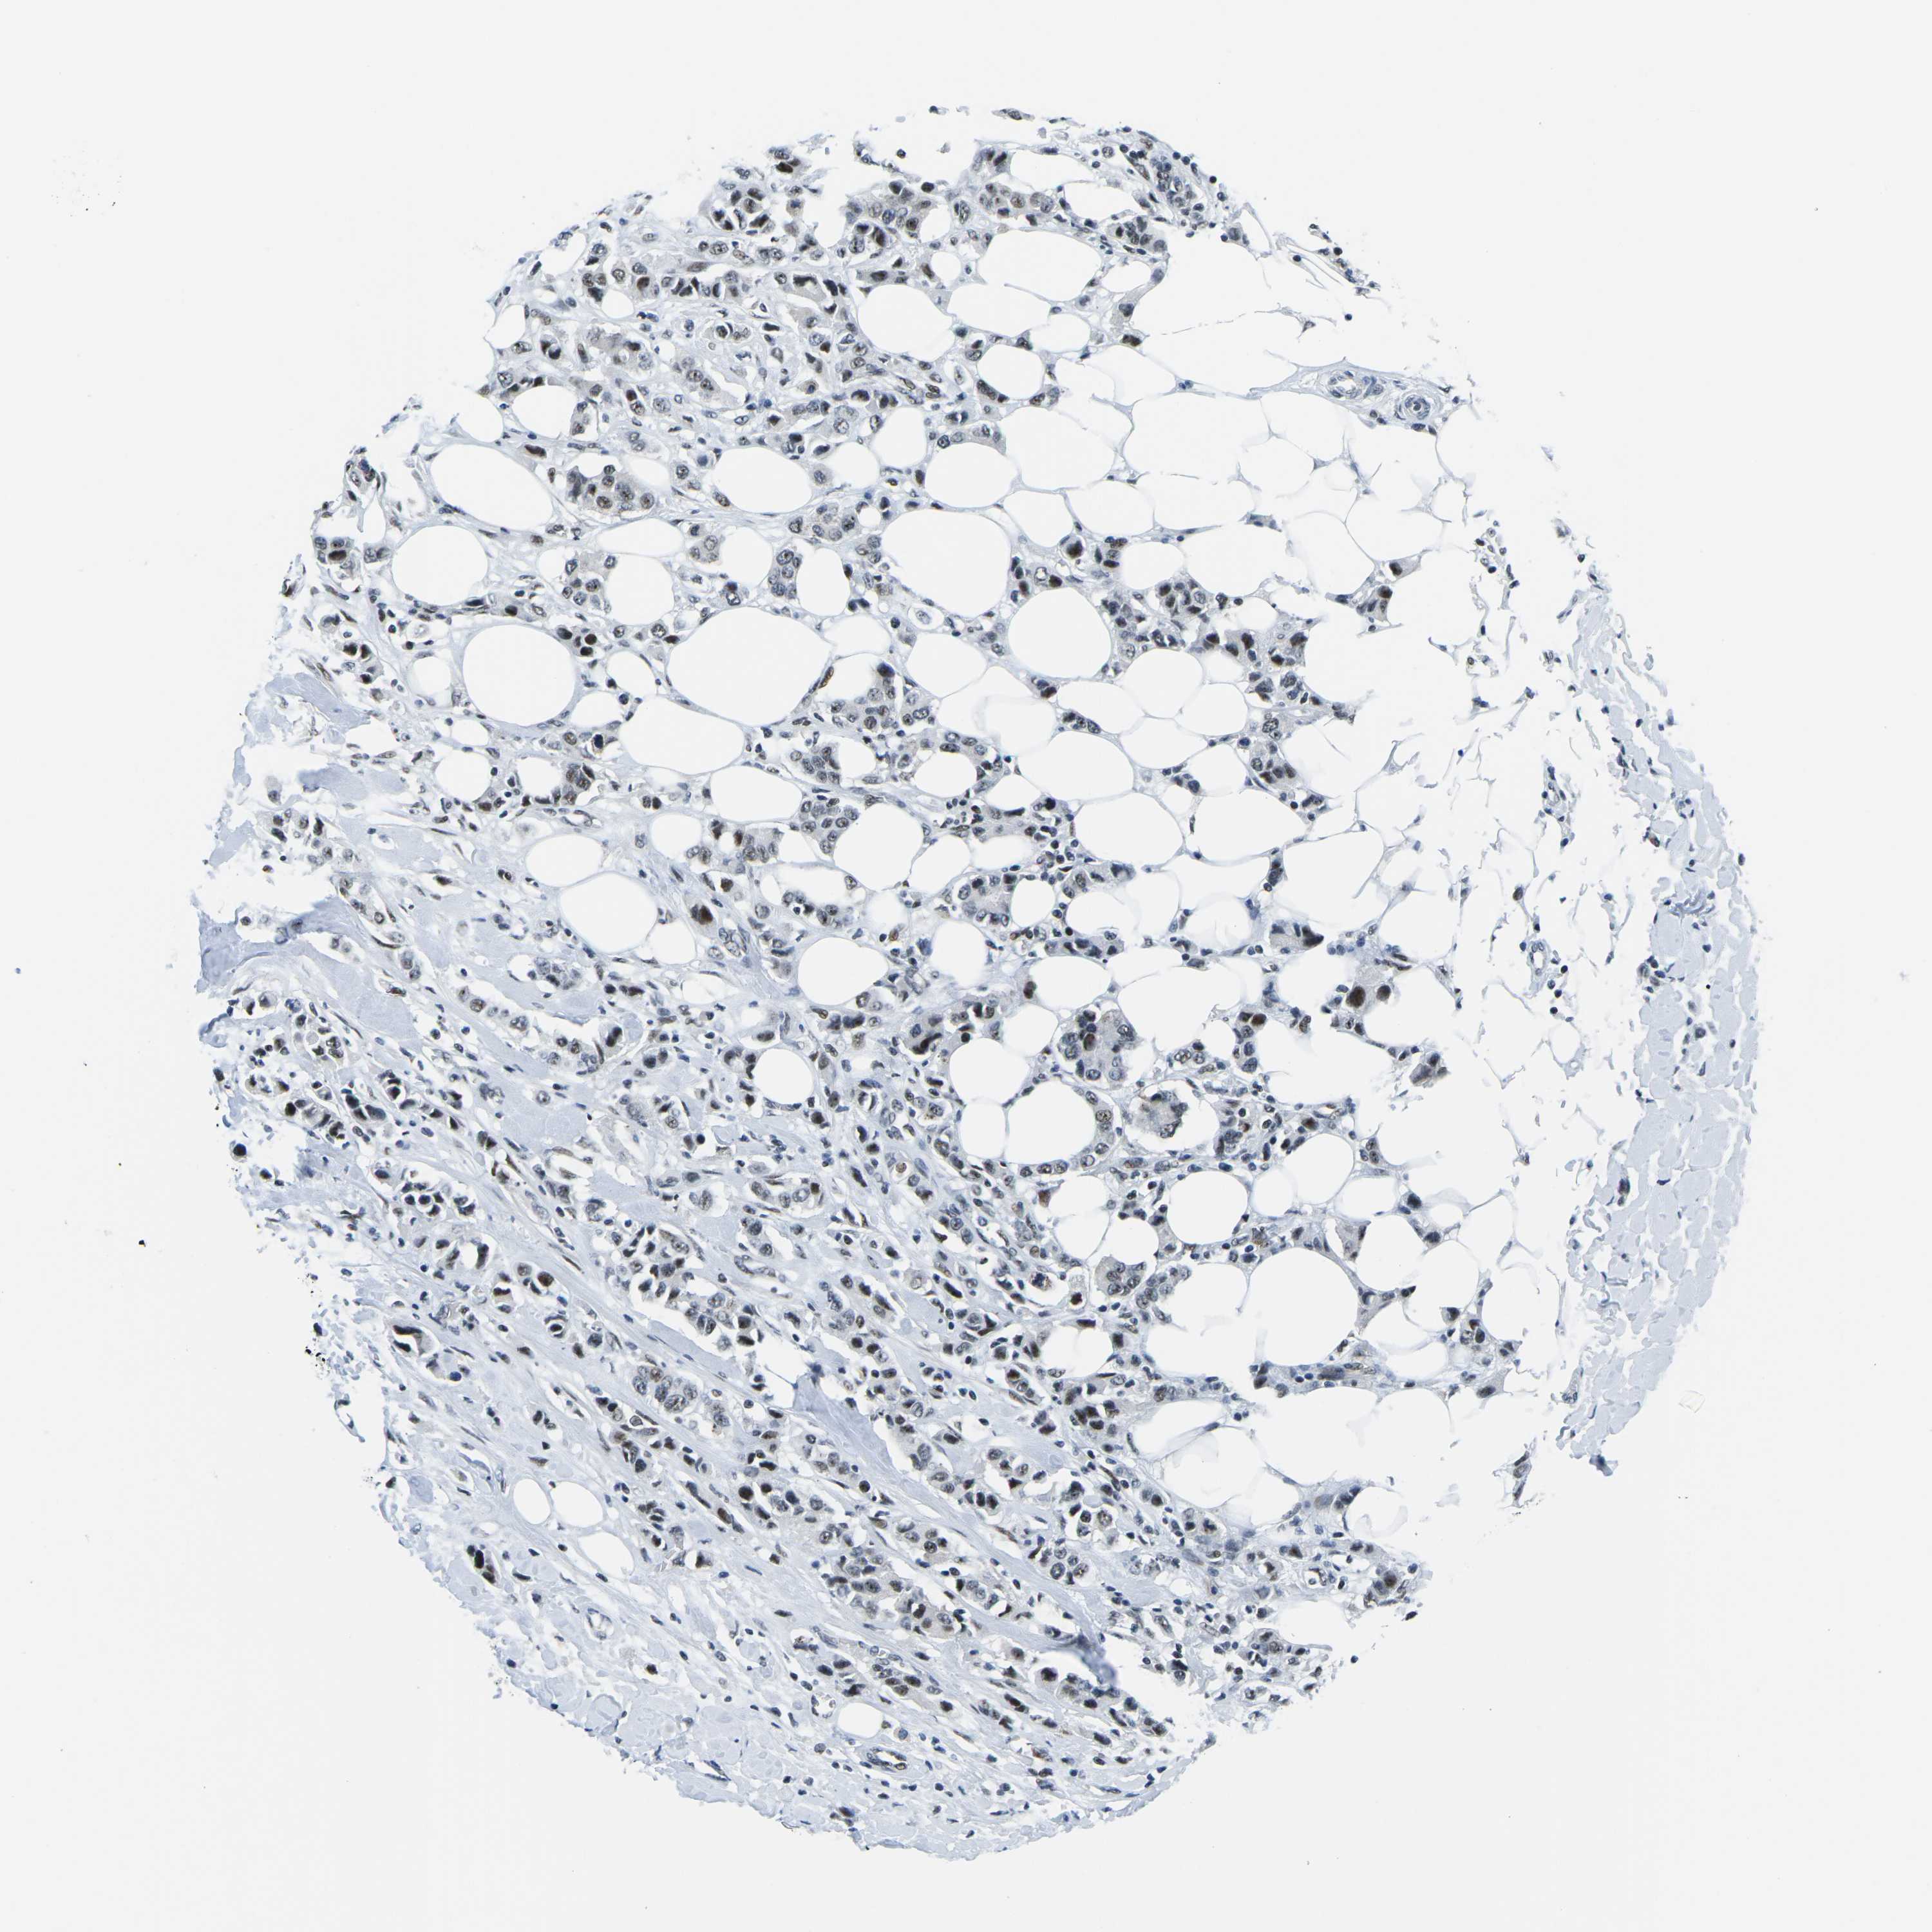

CANCER BREAST CANCER Show tissue menu

BRCA TCGA BRCA VALIDATION PROTEIN EXPRESSION